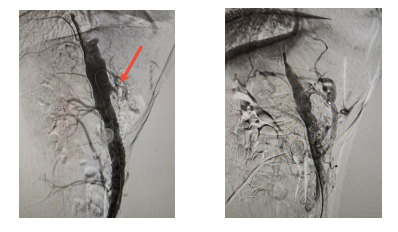

入院后,腹部增强CT检查揭示了病情的严峻性——腹腔干动脉开口处存在严重钙化斑块,造成重度狭窄,血管壁坚硬如石;更为棘手的是,肠系膜上动脉竟异常起源于该狭窄段,并已完全闭塞。两条为肠道供血的关键动脉“命悬一线”。

何创业主任指出,该病例不仅解剖结构罕见,且钙化程度极为严重,常规导丝难以通过,球囊扩张阻力大,支架释放风险高,属于介入治疗中的“硬骨头”。

面对这一高难度挑战,何创业主任带领卫飞鹏医生等团队成员,凭借丰富的复杂钙化病变处理经验,术中精准操控导丝,成功穿透坚硬钙化斑块,顺利开通闭塞的肠系膜上动脉,并采用高压球囊充分扩张后,精准植入支架,成功重建肠道血供“生命线”。